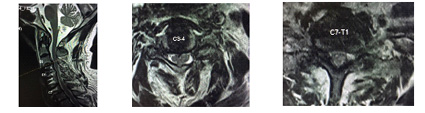

| Gambar 6.Sebelum operasi PSCD, Pasien usia78 tahun, sudah dilakukan operasi di Singapore tahun 2012, terpasang implan C4,5,6,7, pada saat ini terjepit C3-4 dan C7-T1 |

| Gambar 7.Sesudah operasi PSCD C3-4 dan C7-T1, Luka 1 cm, 2 titik. |